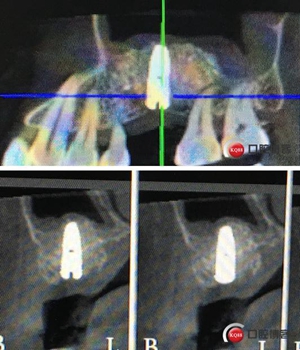

切開(kāi)翻瓣。

植入一顆4.5x11.5mm長(zhǎng)度植體。

植入后X光片。

半年后修復(fù)。